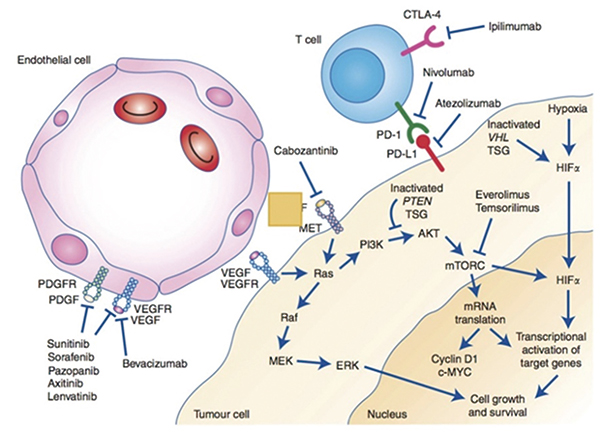

美国希望城综合癌症中心Pal等报告,治疗转移性乳头状肾细胞癌(RCC),多激酶抑制剂治疗卡博替尼对比舒尼替尼的中位无进展生存期(PFS)分别为9.0个月和5.6个月(HR=0.60,95%CI…

美国纪念斯隆·凯特琳癌症中心Motzer等报告,一线治疗晚期肾细胞癌(RCC)物,帕博利珠单抗-Lenvatinib改善了生存结局和缓解率,主要终点中位无进展生存期(PFS)达23.9个月,远…

美国纪念斯隆·凯特琳癌症中心Motzer等报告,与舒尼替尼一线治疗晚期肾细胞癌(RCC)相比,纳武利尤单抗联合卡博替尼有临床意义、疗效持久、生活质量改善。肉瘤样肾细胞癌患者…